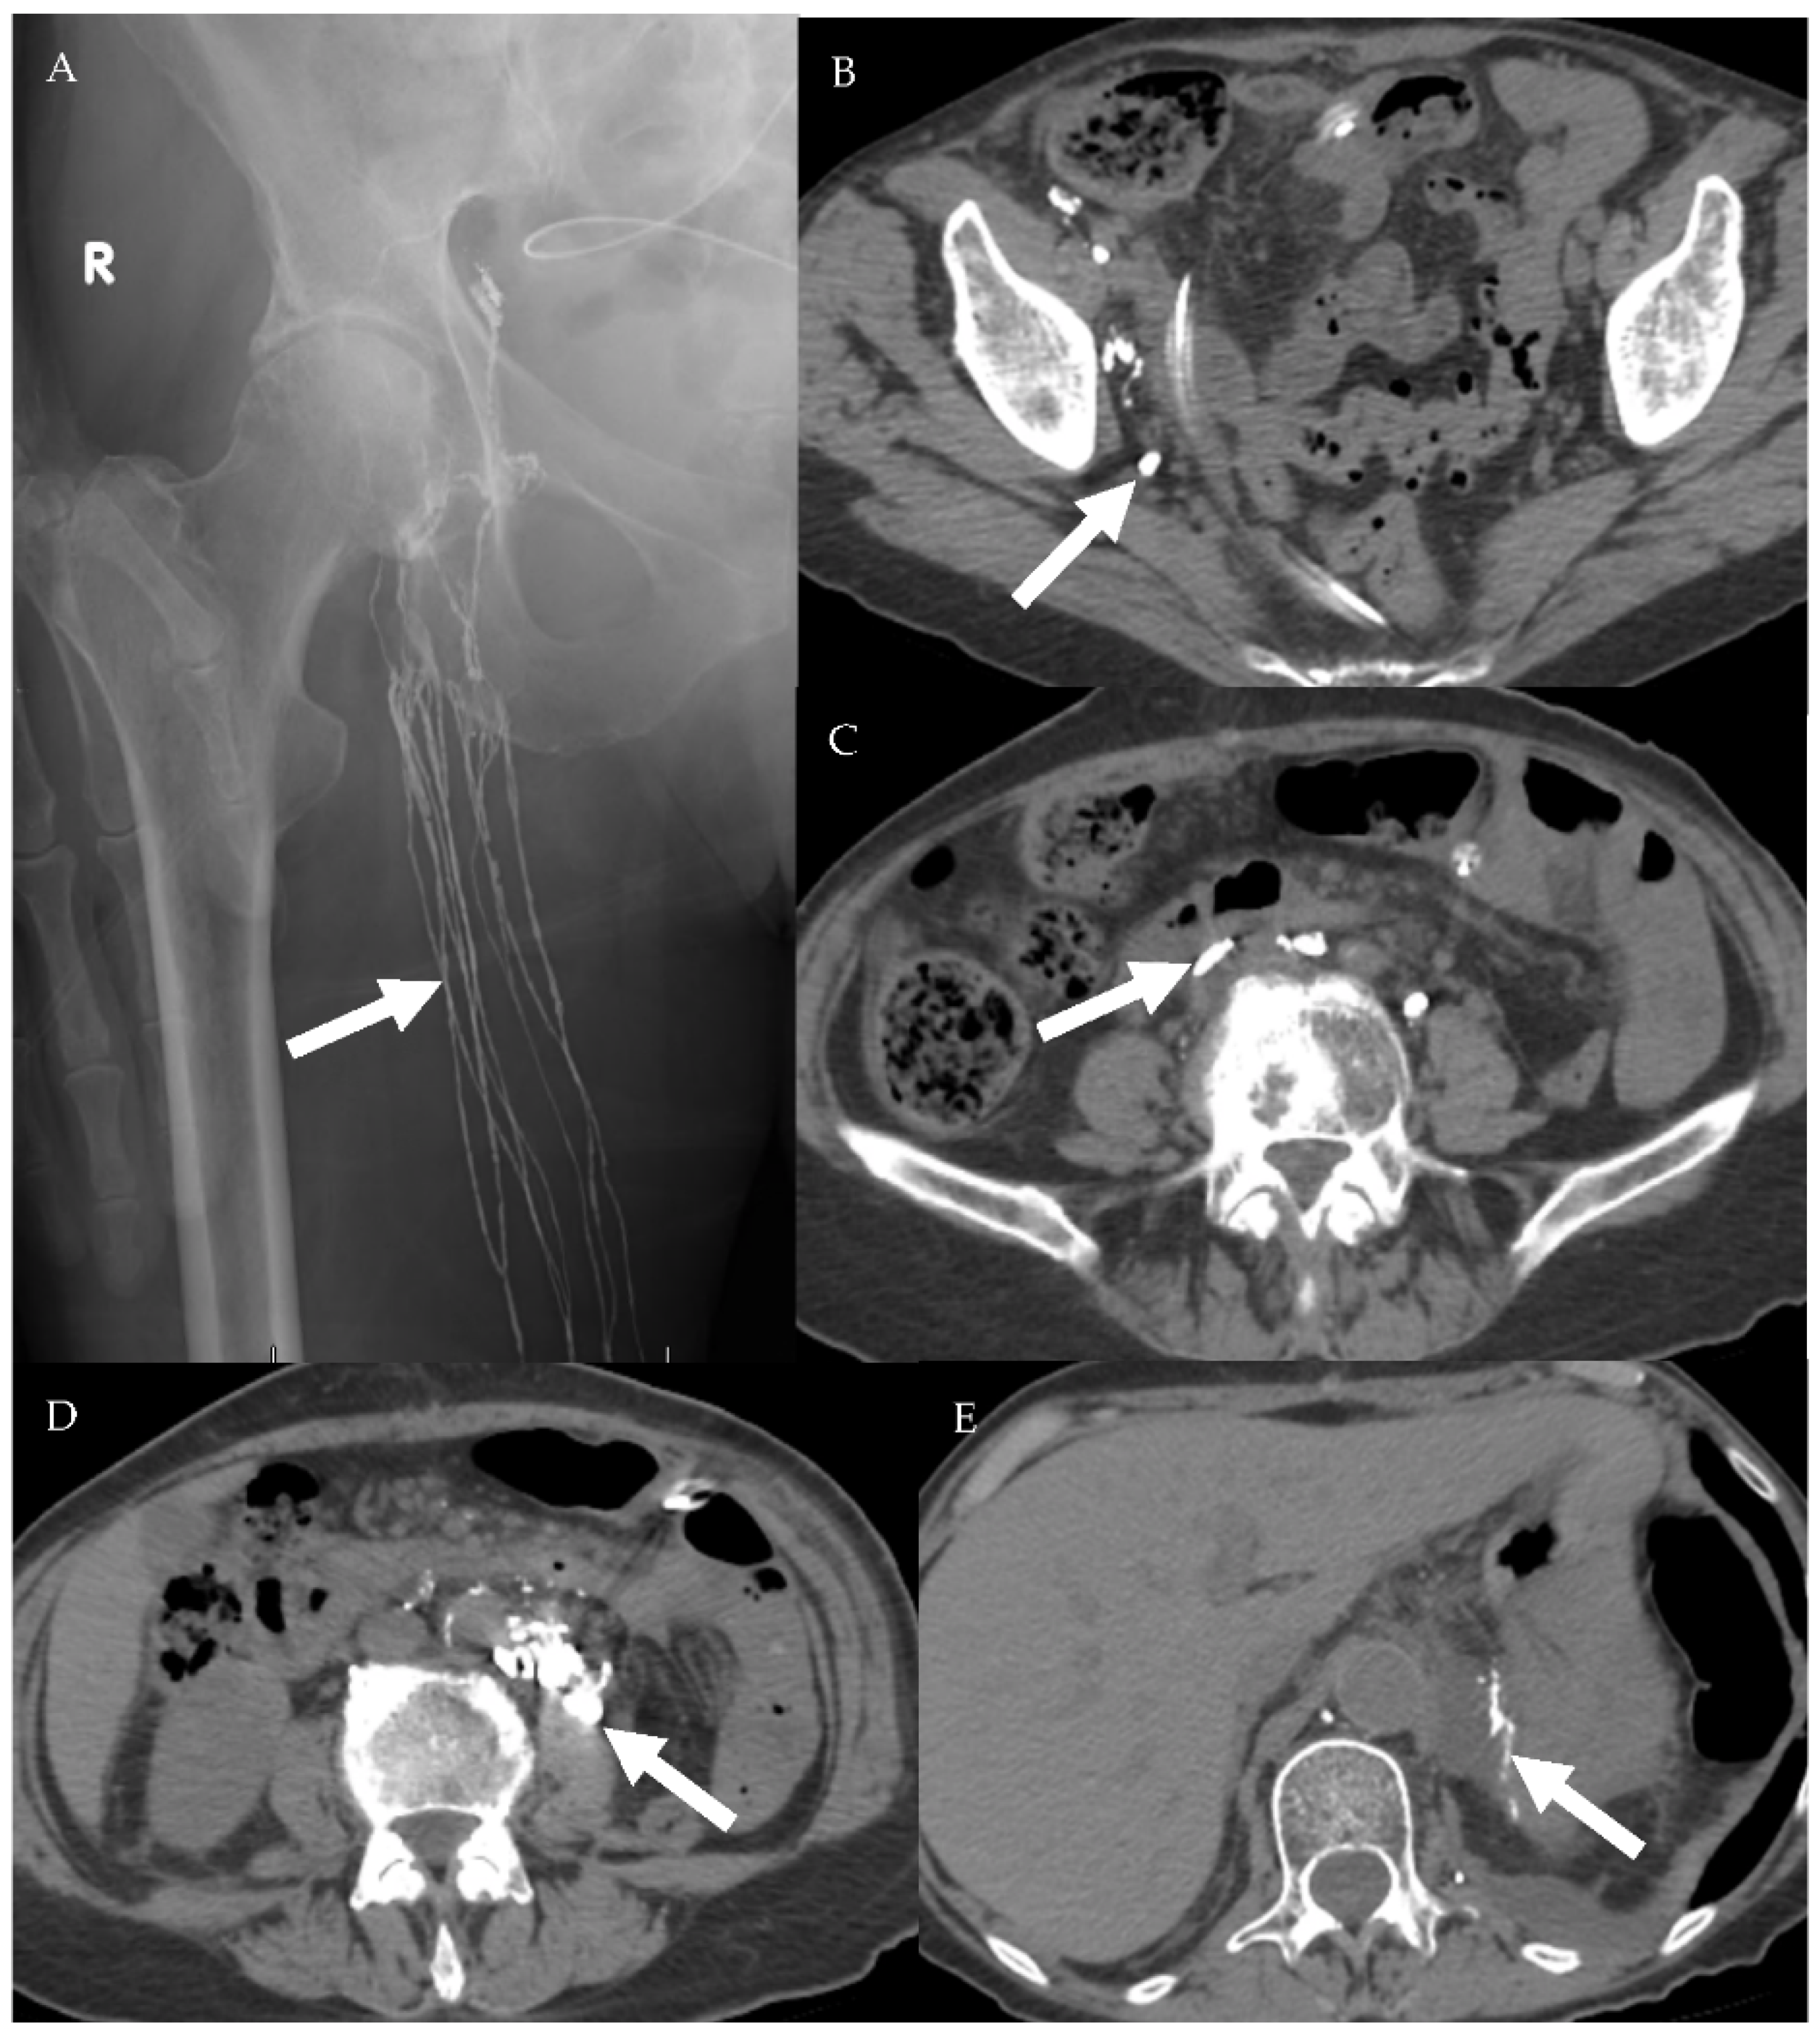

4.2.1. Conventional Lymphangiography (CL)

4.2.2. Magnetic Resonance Lymphangiogram (MRL)